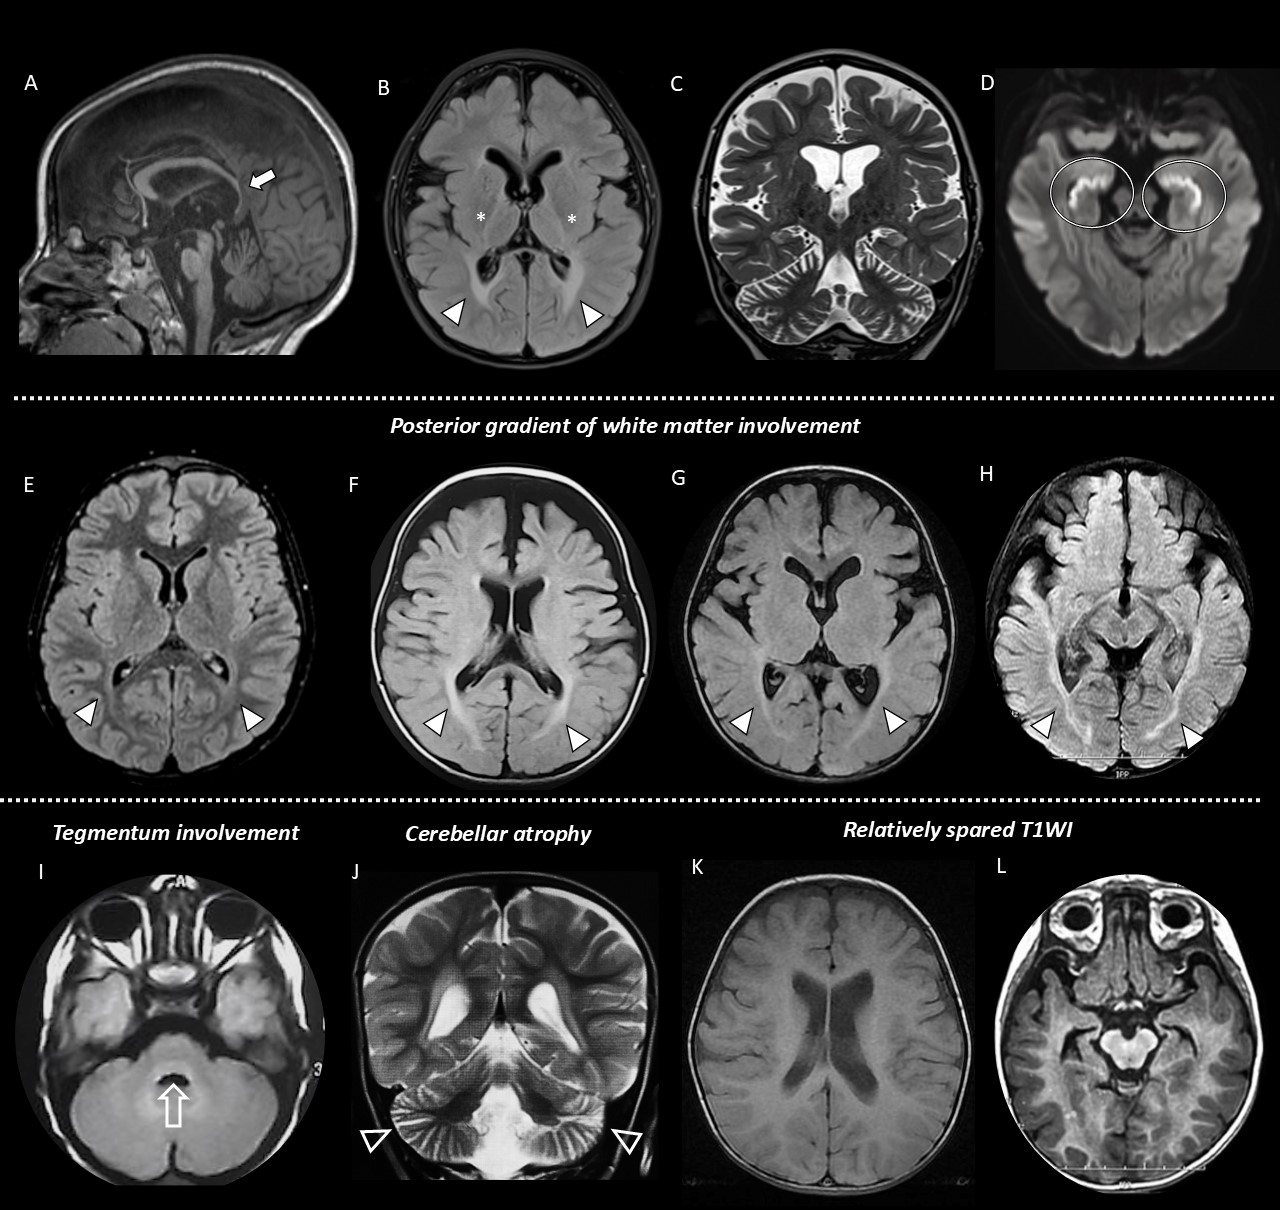

Results: The cohort is composed of 60 patients from 55 families. 45 individuals are currently alive with a mean age of 6.6±4.9 years (range 1.4-18). 19 patients (30%) died between the ages of 3 and 19 years due to the rapidly progressive disease. Premature death at the mean age of 6.0±4.3 was observed in 30% of cases and the mean age of the alive patients is 6.6±4.9. The disease presents with predominantly infantile-onset (88%), moderate (51%) and rapidly (40%) progressive neurological deficit manifesting with global developmental delay (71%) or developmental regression (98%)/stagnation (86%) commonly resulting in limbs spasticity (92%), limb dystonia (73%) and axial hypotonia (73%), feeding difficulties (60%), and joint contractures (45%), scoliosis 17/48 (38%), and epileptic seizures 12/39 (31%). Dysmorphology assessment revealed a consistent facial gestalt in 9/17 patients. Neuroimaging analysis revealed invariable posterior gradient white matter signal changes and diffuse cerebral volume loss (73%) (Fig.1) ACER3 variants identified in the cohort are presented in Fig.2. Functional studies reveal significantly reduced ceramide hydrolysis. Mutant analysis identifies functional hot spots, with in vitro assays showing a 2–40% decrease in ceramidase activity. Lipidomic analysis confirms a 50% increase in ceramide and sphingomyelin levels, alongside reduced sphingosine (Fig.3, 4).

Figure 1